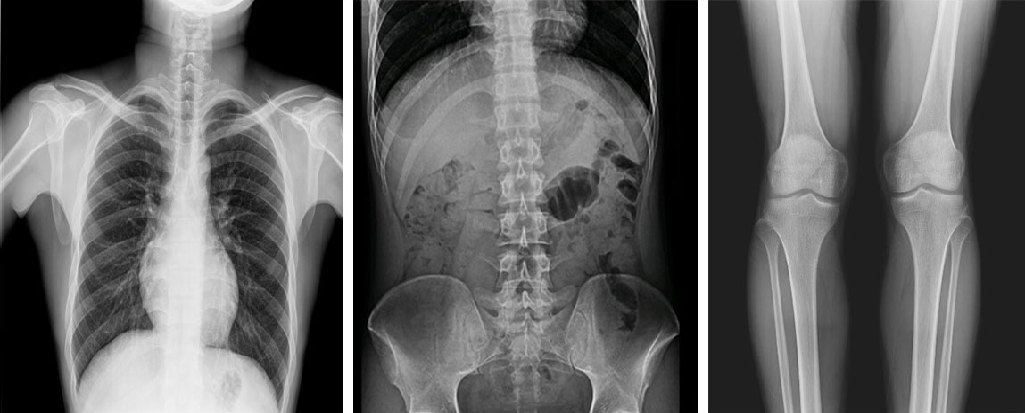

靜態(tài)DR最大的缺陷來自于盲拍,因此造成誤診發(fā)生率高,是保證診斷準(zhǔn)確性的巨大阻礙因素。在靜態(tài)拍片中,部分特殊病灶容易被遮掩而導(dǎo)致漏診,在一些特殊造影上需要憑借醫(yī)生的臨床經(jīng)驗才能獲取有效影像。而動態(tài)DR依靠可視化高速高清點片功能,改變了傳統(tǒng)的盲拍模式。動態(tài)DR在低劑量數(shù)字透視的情況下,能夠進(jìn)行疑似病灶部位點片,極速精準(zhǔn)獲取有效信息,同時可即時回放視頻信息,在臨床上極大地提高了病變的檢出率,降低漏診誤診。

在功能上,動態(tài)DR已不再局限于簡單的拍片功能,而是集數(shù)字化攝影、數(shù)字化透視、數(shù)字化造影、數(shù)字化實時點片于一體,臨床用途廣泛,可應(yīng)用于臨床各科室,如體檢科、內(nèi)科、外科、骨科、創(chuàng)傷科、急診科等。

與此同時,動態(tài)DR的成像視野與精度也勝于靜態(tài)DR。動態(tài) DR17×17 英寸方形幅面進(jìn)行動態(tài)成像,能夠?qū)鹘y(tǒng)動態(tài)造影幅面小的問題全部解決,同時由于幅面較大,臨床操作技師能夠在一個大的幅面下觀察診斷,當(dāng)看到病變部位時實時高清點片,從而很好地捕捉到病變點,也大大降低了檢查時間。